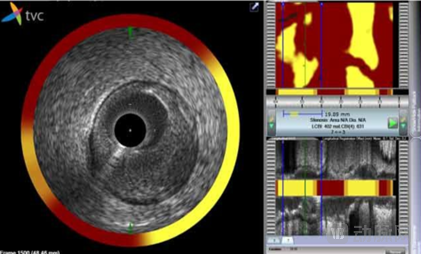

美国 Infraredx:开发全球首款红外 + 血管内超声的冠脉内镜

Infraredx 红外 + IVUS 的冠脉内镜